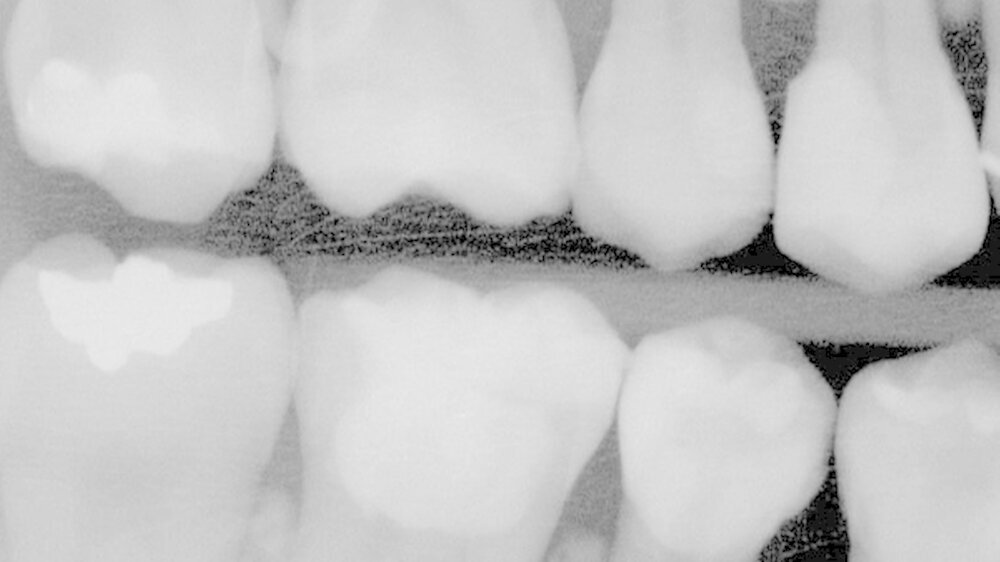

Das Röntgenbild zeigte, dass die Füllungen bei Zahn 45 und 46 nahe an der Pulpakammer lagen. Mit EPT (32/80, 35/80) und thermischen Tests wurde die Pulpavitalität geprüft (normal). Die Diagnose lautete: tiefe Karies. Die Kompositfüllungen wurden daraufhin möglichst substanzschonend ersetzt.

Die Behandlung umfasste zwei Termine (erster: Zahn 46 und 45, zweiter: Zahn 43 und 44). Zur Entfernung der alten Füllungen dienten ein runder und ein zylindrischer Diamantbohrer sowie langsam laufende Hartmetallbohrer und zur Feinbearbeitung der Kavitäten ein Ultraschallinstrument. Nach selektiver Schmelzätzung applizierte man das Adhäsiv XP BOND®. Das Dentin wurde durch SDR ® ersetzt. Dann wurden mit ceram.x one® d3 und e2 jeweils der Rest der Kavität und die Höcker restauriert. Finiert und poliert wurde mit dem Soflex Poliersystem.